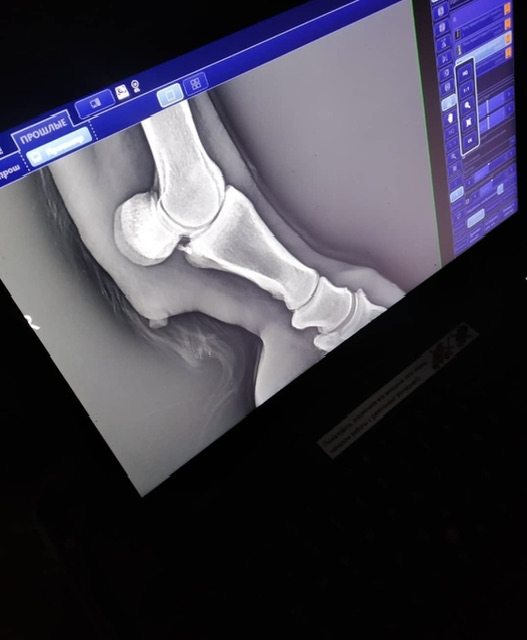

Мерин 8 лет, хромает 2 года (снимки сделаны 2 года назад

Кто может подсказать диагноз? Правая передняя нога